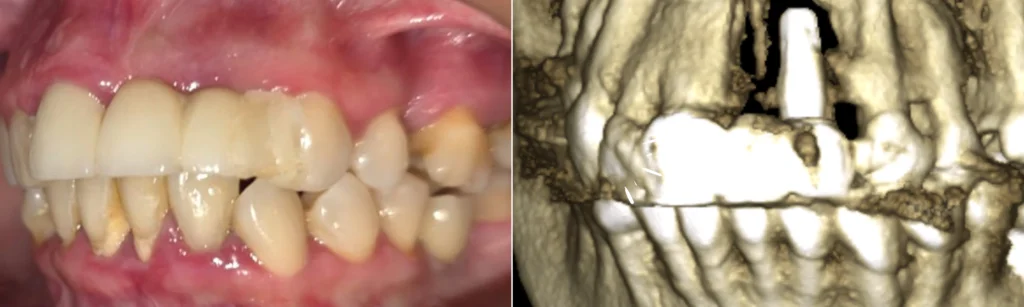

El Caso Real: «No Hay Hueso, No Hay Solución»

Un paciente después de visitar varios especialistas. Su diagnóstico:

- Implante convencional fracasado en zona anterosuperior (crítica para la estética)

- Pérdida total del hueso de soporte

- Diagnóstico unánime: imposible colocar otro implante en el mismo lugar

- Alternativa ofrecida: prótesis removible (incómoda y poco estética)

Las técnicas de regeneración ósea convencionales no eran viables. La ausencia de paredes óseas hacía cualquier intento de regeneración de dudoso éxito, con cirugías complejas y meses de espera sin diente provisional.

En solo 30 minutos, realizamos:

- Explantación del implante afectado y desinfección minuciosa del área

- Colocación de 3 implantes monofásicos córticobasales con técnica guiada

- Impresión digital inmediata con escáner intraoral

- Diseño y fabricación de prótesis fija provisional

Resultado: Paciente salió el mismo día con:

- Implantes seguros y estables

- Prótesis fija y estética

- Sonrisa y funcionalidad recuperadas